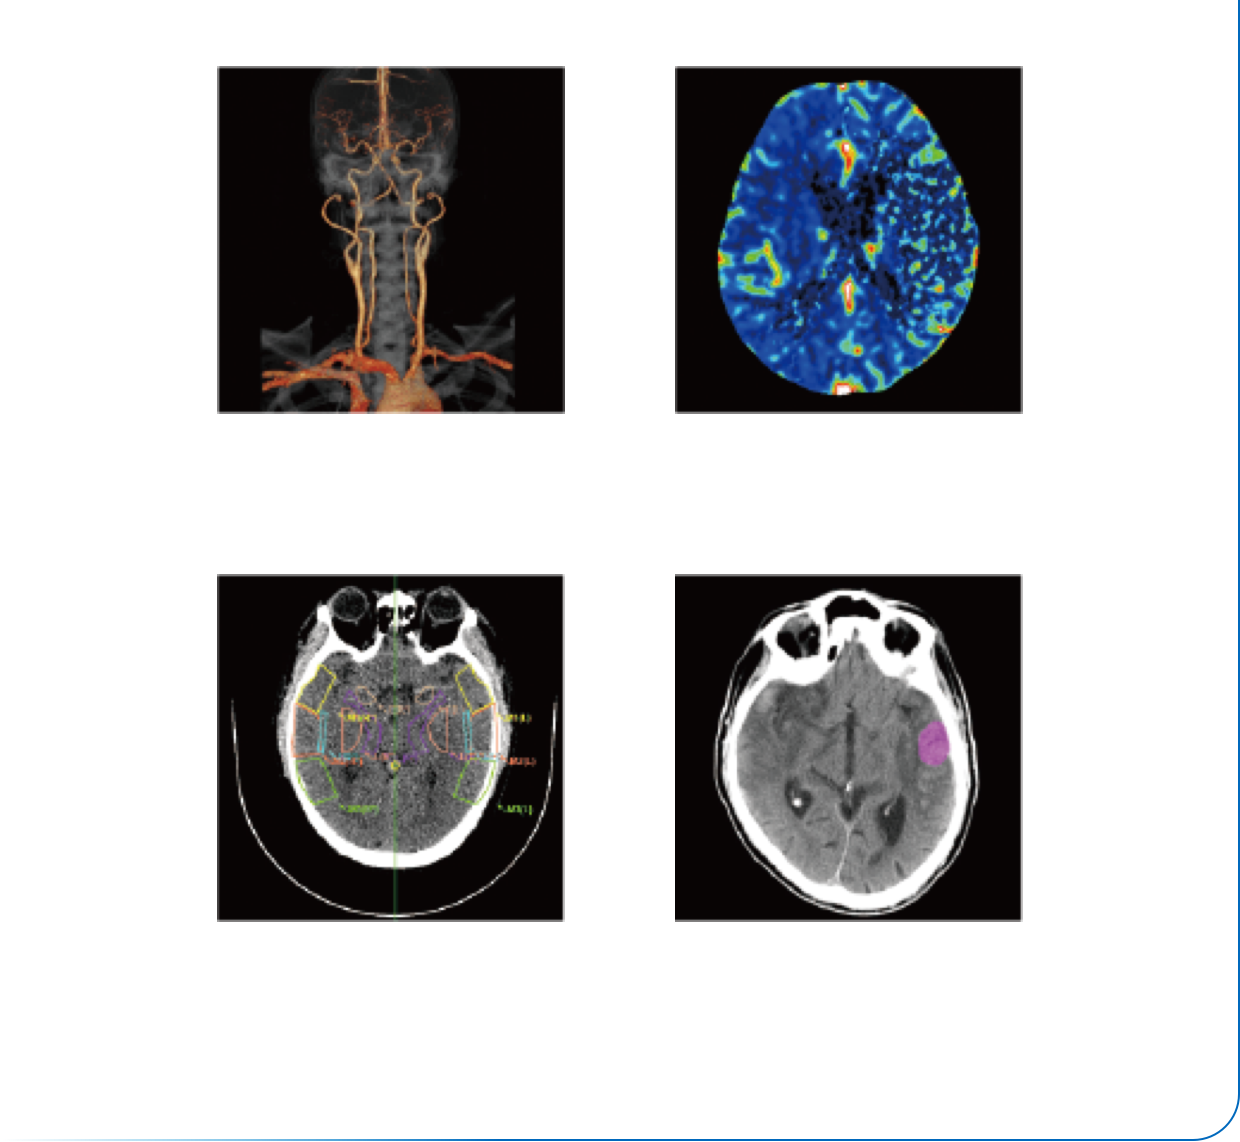

智能门控扫描

智能心律识别

智能期相选择

智能扇区重建

智能冠脉运动伪影补偿